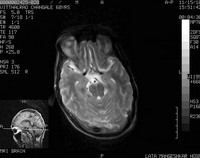

AbstractRamsay Hunt syndrome (also termed Hunt's Syndrome and herpes zoster oticus) is a herpes zoster virus infection of the geniculate ganglion of the facial nerve. It is caused by reactivation of herpes zoster virus that has previously caused chickenpox in the patient. Ramsay Hunt syndrome results in paralysis of the facial muscles on the same side of the face as the infection so, the virus infects the facial nerve that normally innervates the muscles of the face. Ramsay Hunt syndrome is typically associated with inflamed vesicles in or around the ear and sometimes on the roof of the mouth or tongue. Here we are presenting a case of 70 year old male had Ramsay Hunt syndrome with multiple cranial nerves' involvement (CN IX & X). Treatment with prednisolone and valacyclovir was given within the first three days of facial paralysis to the patient to achieve complete recovery. IntroductionRamsay Hunt syndrome is defined as varicella zoster virus(VZV) infection of the head and neck that involves the facial nerve, often the seventh cranial nerve (CN VII). Other cranial nerves (CN) might be also involved, including CN VIII, IX, V, and VI (in order of frequency). This infection gives rise to vesiculation and ulceration of the external ear and ipsilateral anterior two thirds of the tongue and soft palate, as well as ipsilateral facial neuropathy (in CN VII), radiculoneuropathy, or geniculate ganglionopathy. After chickenpox, VZV remain latent in neurons of cranial nerve and dorsal root ganglia. Subsequent reactivation of latent VZV can result in localized vesicular rash, known as herpes zoster. VZV infection or reactivation involving the geniculate ganglion of CN VII within the temporal bone is the main pathophysiological mechanism of Ramsay Hunt syndrome. Here we are presenting a rare case of Ramsay hunt syndrome with multiple cranial nerve involvement. Case reportA 70 year old male, right handed, farmer by occupation presented with fever and erythematous rash over external ear since 3 to 4 days, difficulty in swallowing, deviation of angle of mouth to left side since 2 days , unable to close right eye , hiccoughs and headache since 1 day. There was no history of any ear discharge, convulsion, unconsciousness or weakness in any limb. Patient denies any history of hearing loss. There was no history of diabetes mellitus, hypertension, pulmonary tuberculosis, patient also denies any history of promiscuous behavior. On general examination patient was conscious oriented with time, place and person, Afebrile, P - 84/min regular RR-20 / min, BP- 100/60 mm Hg, Pallor present. On cutaneous examination multiple grouped vesicular eruptions on erythematous base presented on external ear and posterior aspect of right ear (Figure1&2). On systemic examination within normal limits. CNS examination within in normal limits except VII, VIII, IX, X cranial nerves were involved. Patient had right side palpebral fissure widen than left, incomplete closure of right eye, nasolabial fold flattening on right side, angle of mouth deviated to left side, epiphora from right eye, taste sensation of anterior 2/3rd of tongue was absent suggestive of VII cranial nerve(facial nerve) involvement. Rinne's test positive in both ears, Webers test showed reduced hearing on right ear suggestive of sensorineural hearing loss of right side of VIII cranial nerve(Vestibulocochlear nerve) involvement. Soft palate movements on right side were absent, gag reflex absent on right side, uvula was deviated to left side suggestive of IX & X cranial nerve (Glossopharyngeal & Vagus nerve) involvement. Other cranial nerves were normal. Motor function & delayed tendon reflexes were normal. Sensory function was normal. Cerebellar functions were normal. Fundus examination was within normal limit. On clinical examination was consistent with acute onset lower motor neuron type right sided VII,VIII, IX, X cranial nerve palsy due to reactivation of herpes zoster. Then we investigated the patient as CBC- Hb-10 mg/dl, KFT- Urea -30mg%, Sr.creatinine-0.8%, LFT- normal, HIV 1 &2 - negative, blood sugar (random)-104 mg/dl. Serology results for herpes simplex virus 1 and 2 were positive for IgG antibodies and negative for IgM antibodies. Varicella-zoster virus (VZV) IgG antibodies were positive, but IgM antibodies was positive. MRI brain revealed age related mild cerebral atrophy with neurodegenerative changes. Soft tissue intensity was seen in right mastoid air cells and in the inner cavity which on post contrast study showed minimal enhancement with edematous VIIth and VIIIth nerve complex suggestive of inflammatory focus in clinically diagnosed case of Ramsay Hunt Syndrome (Figure 5). The patient was treated with tablet valacyclovir 1gm 3 times per day for 7 days along with tab prednisolone 40 mg OD in tapering dose for 1month, Ryle's tube feeding was done for 10 days, Physiotherapy of facial nerve was done for 1 month, eye bandage was put for 10 days. At the end of 1 month remarkable improvement was observed (Figure 1,2,3,4 & 6,7 shows pre treatment & post treatment photograph). He is being followed up till today.